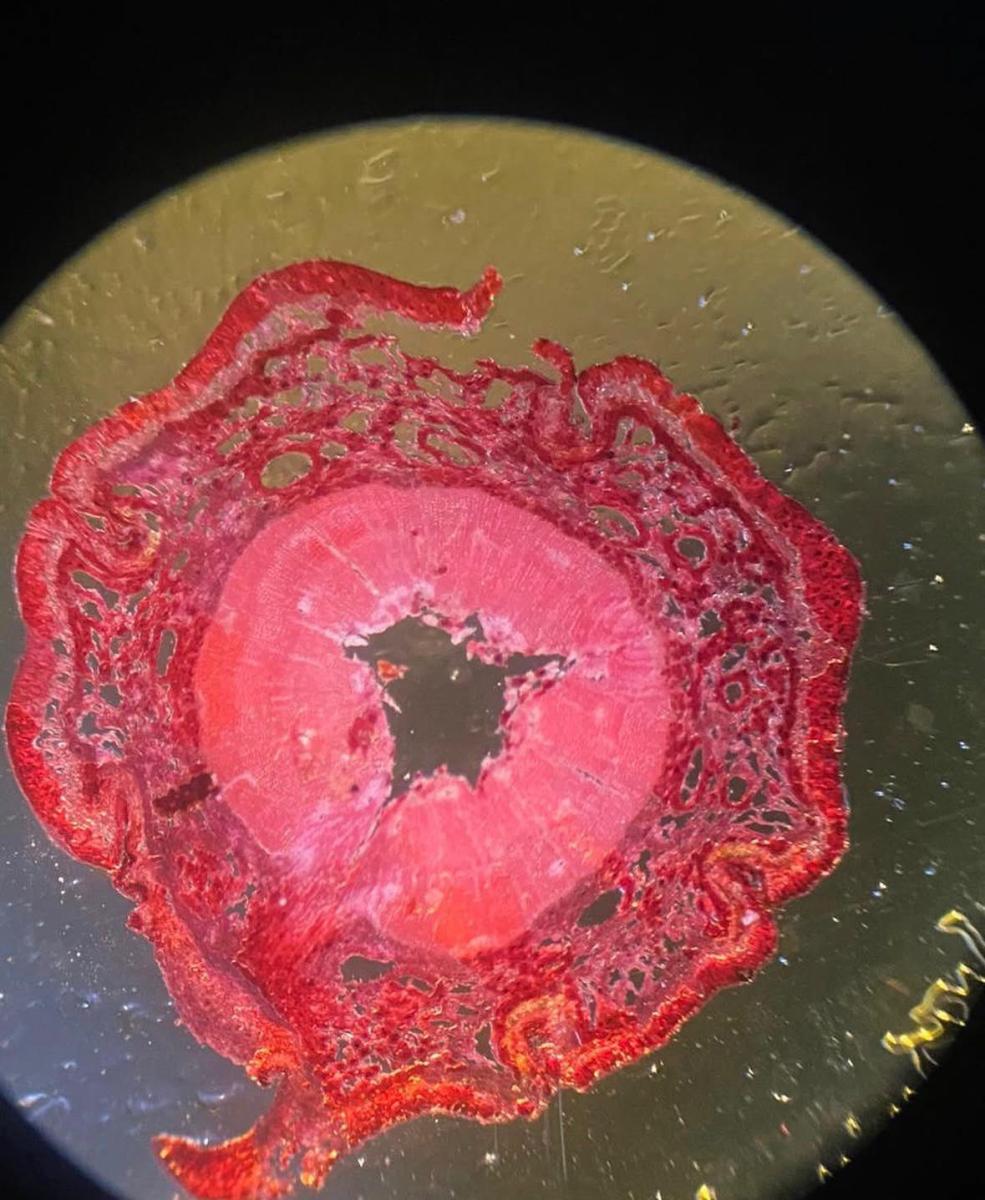

1. Приручит бактерии, препарирует рака и сельдь, изучит социальное поведение крыс и выделит молекулы ДНК, чтобы понять, как они работают.

2. Научится микроскопировать и препарировать на настоящем оборудовании — ничуть не хуже первокурсника биофака.